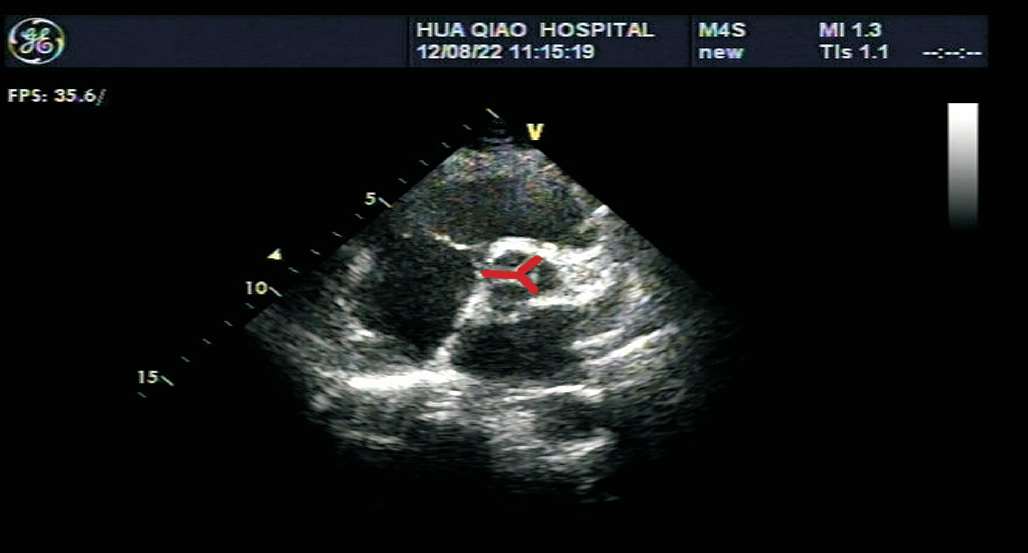

患者取左侧卧位或平卧位,探头置于胸骨左缘第2~3 肋间,声束垂直于胸骨旁左心室长轴切面。在此切面可观察主动脉瓣的形态、厚度、回声强度及开闭状态,右心室流出道与肺动脉干有无增宽、狭窄,降主动脉与肺动脉之间有无异常通道,肺动脉瓣的形态及活动(见图1-27)。正常主动脉瓣呈三瓣叶,收缩期开放为“▽”形,舒张期关闭为“Y”形(见图1-28)。

图1-28 心底大动脉短轴切面主动脉瓣呈三瓣叶,舒张期关闭为“Y”形